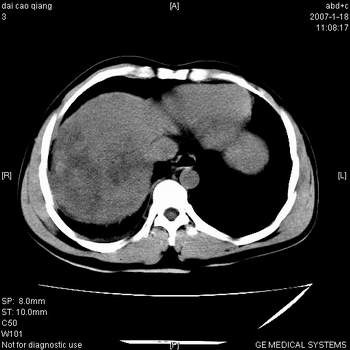

符合巨块型肝癌表现:

1、平扫低密度,增强后表现为快进快出。

2、动脉期可见迂曲的动脉供血血管

3、并可见门静脉右支癌栓形成

4、可见假包膜

5、腹主动脉旁结节影,考虑肿大淋巴结。

典型的肝右叶巨块型肝癌破裂、门脉瘤栓形成。

肝右叶巨大不均匀低密度肿块,前缘有假包膜,增强明显的呈快进快出表现,门脉右支有癌栓,病人虽然年轻但还是首先考虑肝右叶巨块形肝癌,病人血象高只能说有合并感染。不支持肝脓肿。

肝右叶巨块型肝癌破裂、门脉瘤栓形成。